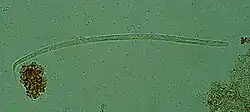

Photomicrograph (glycine mount) of several O. volvulus individuals

Onchocerca volvulus parasites obtain nutrients from the human host by ingesting blood or by diffusion through their cuticle. They may be able to trigger blood-vessel formation because dense vascular networks are often found surrounding the worms.[6] They are distinguished from other human-infecting filarial nematodes by the presence of deep transverse striations.[7]